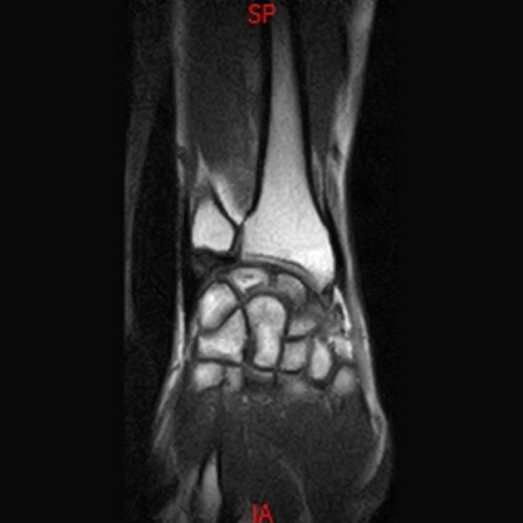

• Resonancia NORMAL TOBILLO SAGITAL T1

• Resonancia NORMAL MUÑECA COR T1

• Resonancia NORMAL MUÑECA COR T1 3D FATSAT